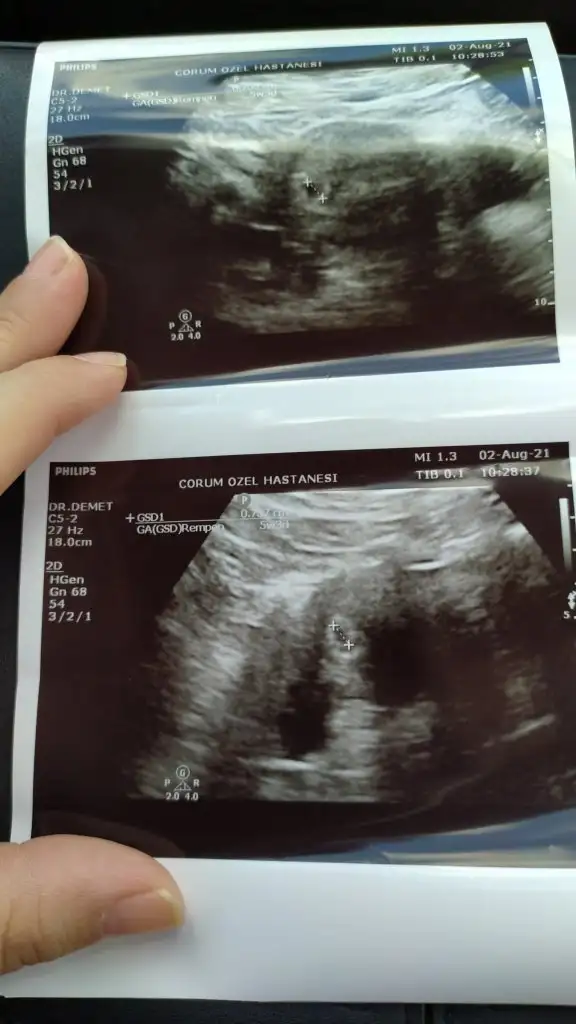

Sağlıkla kucağına almayı nasip etsin canım beta kaçtı acaba kese göründüğünde5+3 deyim kizlar kese gözüktü çok şükür betası düşük olan arkadaşlar yada hızlı ilerlemeyenler hiç kafaya takmayin

Hayırlı olsun canım Allah sağlıkla kucağına almayı nasip etsin. Ben de bgn o lekelenme için gidicem. 4+6 ama keşke gözükse benim de gitmişken5+3 deyim kizlar kese gözüktü çok şükür betası düşük olan arkadaşlar yada hızlı ilerlemeyenler hiç kafaya takmayin

Yaaa maşallah5+3 deyim kizlar kese gözüktü çok şükür betası düşük olan arkadaşlar yada hızlı ilerlemeyenler hiç kafaya takmayin